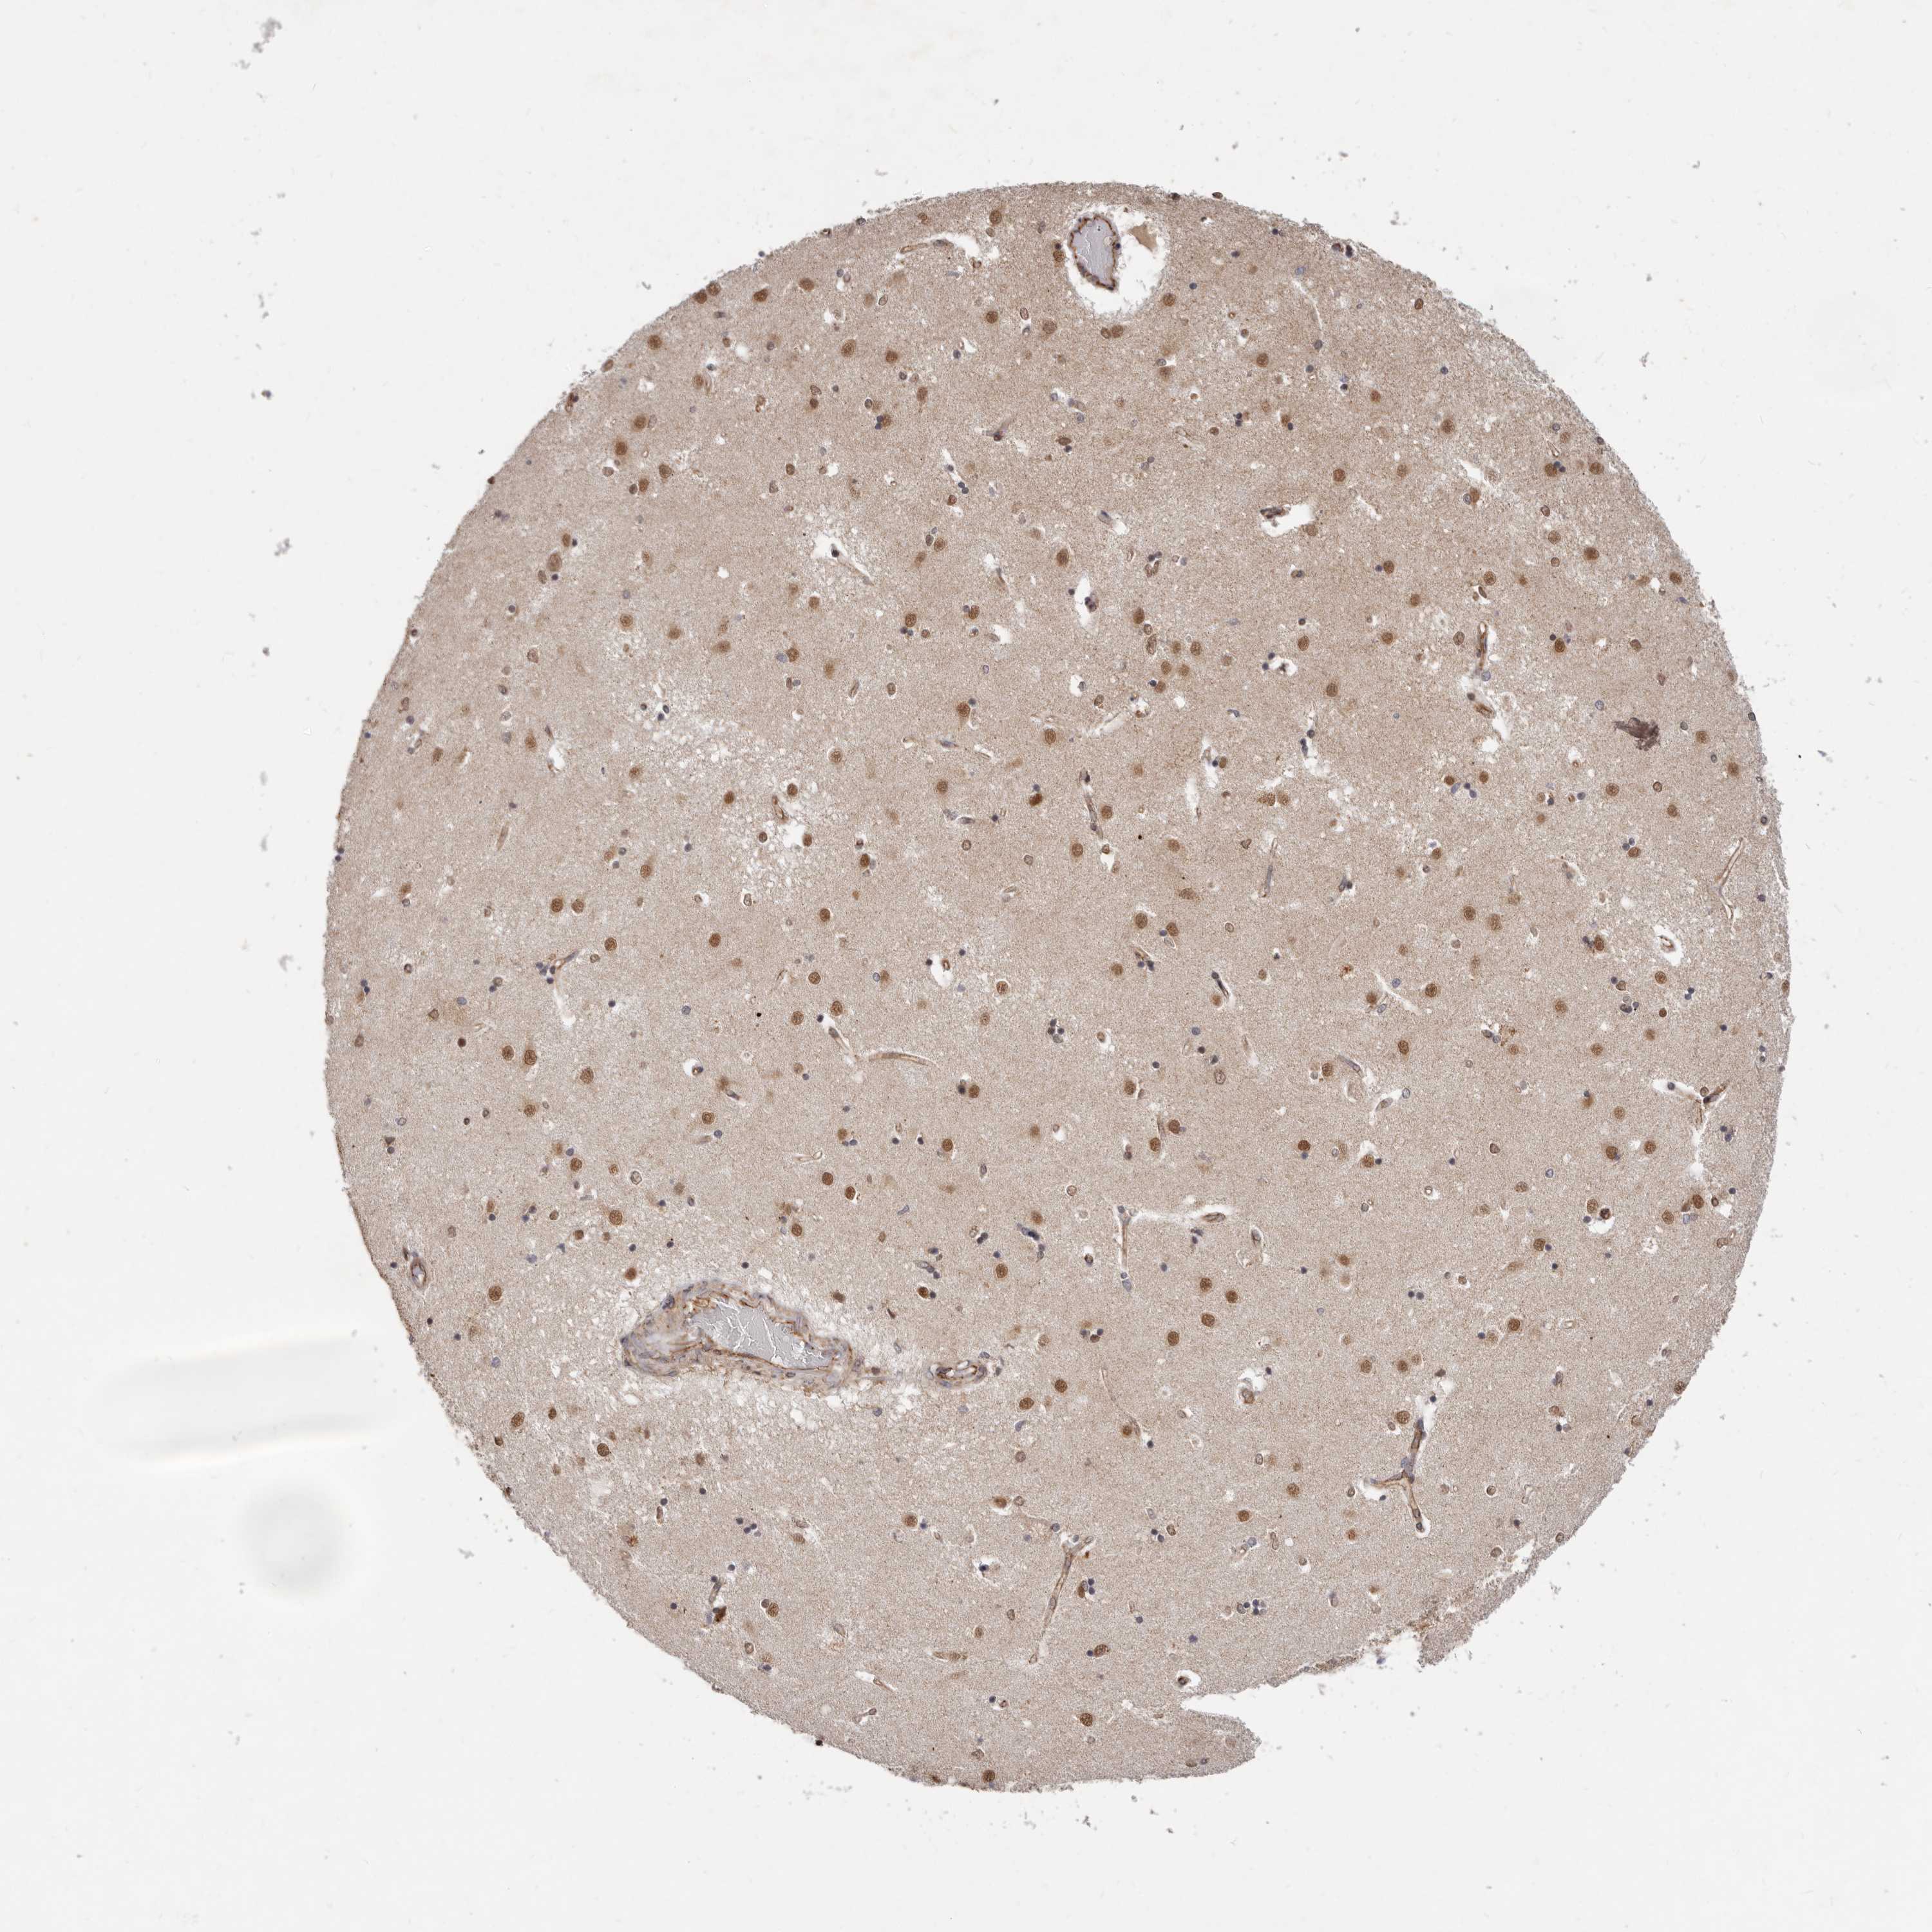

Antibody staining in the annotated cell types in the current human tissue is reported as not detected, low, medium, or high. This score is based on the staining intensity and fraction of stained cells.